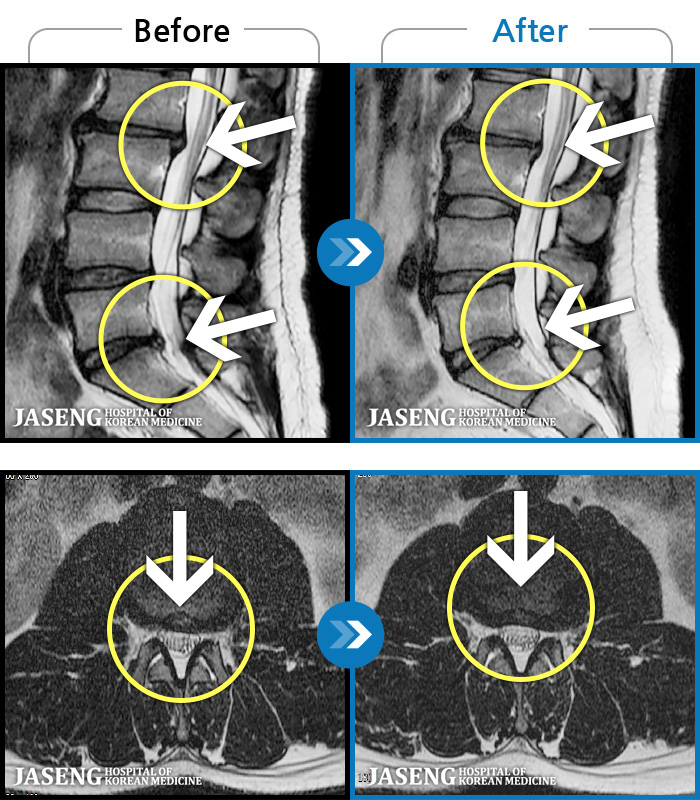

- MRI ġ

MRI ġ

1,299 MRI ũ ʸ Ȯϼ.